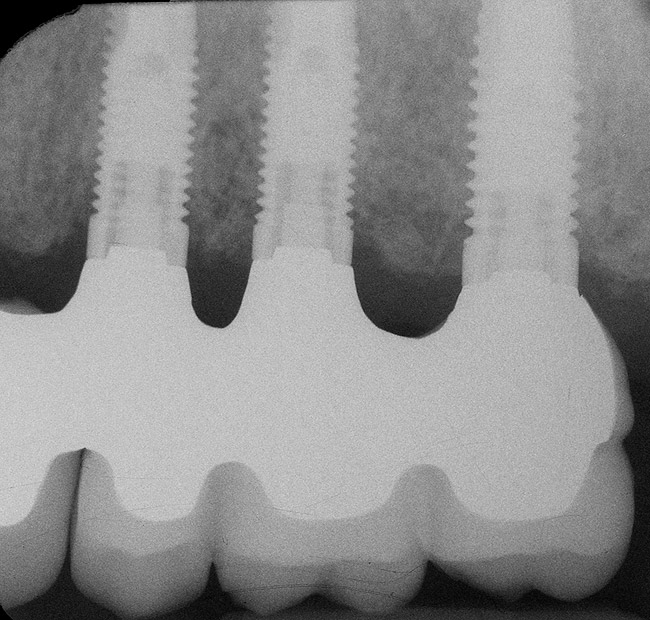

In overdenture therapy, prosthetic design can be divided into two groups: stress-broken and rigid. Stress-broken prostheses require fewer implants, with attention to biomechanical design features to allow for rotation (stress-breaking) of the prostheses around the implant locations. These prostheses are essentially tissue-supported and implant-retained. They replace the adhesive/glue, providing needed retention, comfort, and support. An example would include two implants in site Nos. 23 and 26, with either solitary anchor systems (ball or stud attachments) or a splinted bar-overdenture design (Figure 9 through Figure 11). Masticatory function is improved and patient satisfaction increased. Rigid prostheses require multiple implants, with the forces being transferred from the supra-infrastructure directly to the implants. These prostheses are implant-supported and implant-retained. The design can be removable or fixed (Figure 12 through Figure 16), depending on patient- and operator-mediated preferences.24-27 Within the fixed group of prostheses, materials used may vary from acrylic-fused-to-metal, porcelain-fused-to-metal, or all-ceramic. The cost of these material choices varies significantly, with acrylic options providing the most affordable, entry-level approach for the patient.14